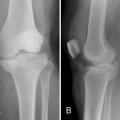

Gonarthrose post traumatique

GONARTHROSE